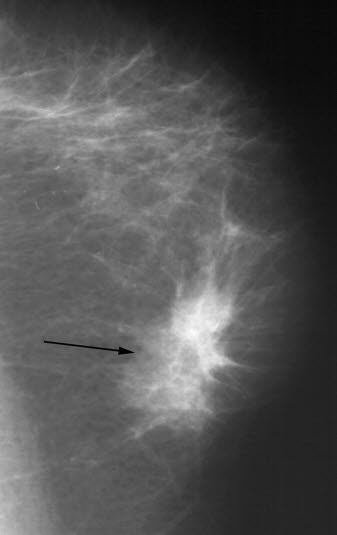

Godartede fortetninger som cyster og bindevevsknuter (fibroadenomer) er vanligvis runde og klart avgrensede. Ondartede fortetninger er vanligvis uregelmessige med uklar avgrensning og innvekst i omgivende vev, ofte med økt antall blodkar. Forkalkninger kan ses som små spredte saltkorn (mikrokalsifikasjoner), og enkelte typer forkalkninger kan være uttrykk for kreftsvulst. Sannsynligheten for at det er ondartet, øker når forkalkningene er samlet. Forskyvning av tilgrensende brystvev og fortykkelse av hud kan også være krefttegn. En del forandringer i brystvevet kan være vanskelige å fortolke og krever supplerende undersøkelser.

Røntgenbildet viser kjertler, melkeganger og bindevev mot en bakgrunn av fett. Ved typiske forandringer kan røntgenlegen skille godartet fra ondartet forandring. Mens godartede forandringer skyver normalt brystvev tilside når de vokser, kan ondartede forandringer vokse inn i omliggende brystvev. Utseende av svulsten og forkalkninger kan også gi viktig tilleggsinformasjon. Tidligere røntgenbilder av brystene er verdifulle til sammenligning når røntgenlegen vurderer de nye bildene. Supplerende ultralyd kan være avklarende, og gjøres som regel dersom det er spesifikke forandringer eller spesielle grunner til mistanke som ligger bak ønsket om undersøkelsen.